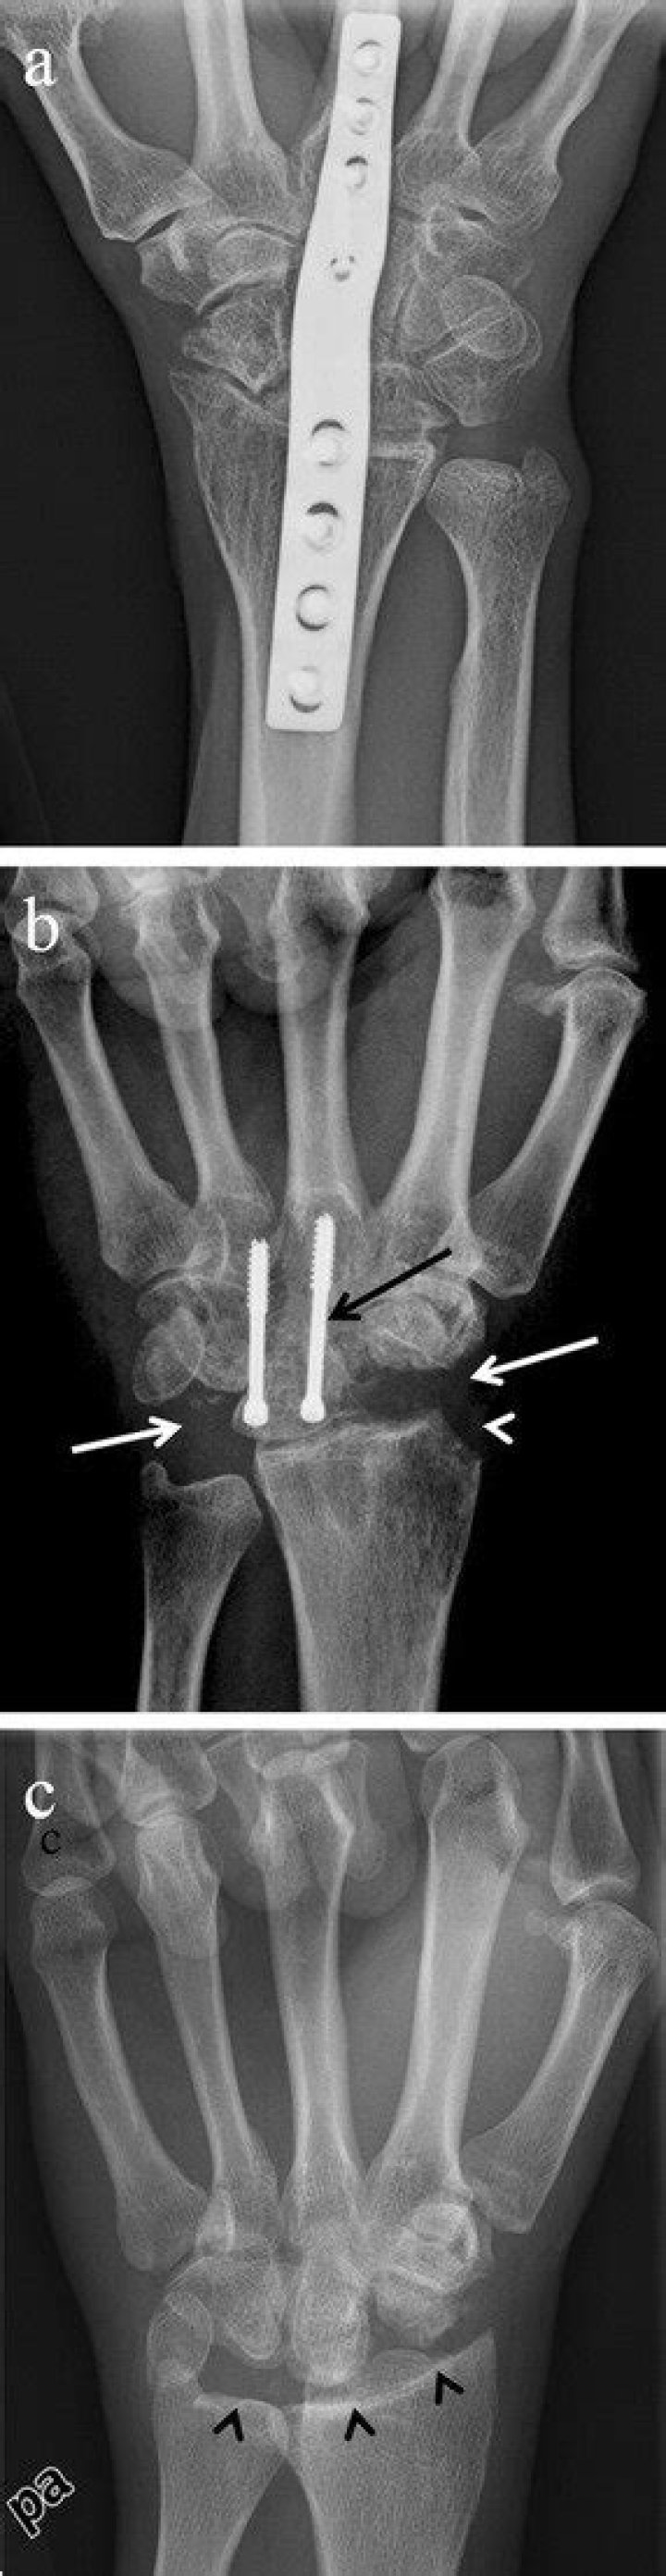

How do you treat a SLAC wrist

Scapholunate advanced collapse (SLAC) of the wrist is the most common pattern of degenerative arthritis in the wrist. The hallmark of SLAC is scaphoid or scapholunate ligament injury with collapse on the radial side of the wrist. Watson and Ballet coined the term SLAC wrist in 1984.

What is Stage 3 SLAC wrist?

Stage III SLAC wrist entails sclerosis and joint space narrowing between the lunate and capitate. Eventually, the capitate will migrate proximally into the space created by the scapholunate dissociation.

What is SLAC surgery?

A SLAC reconstruction involves excision of the scaphoid and arthrodesis of the capitate, lunate, hamate, and triquetrum. Two parallel dorsal transverse incisions, a lazy S incision, or a central longitudinal incision over the distal radiocarpal joint and styloid process is made.